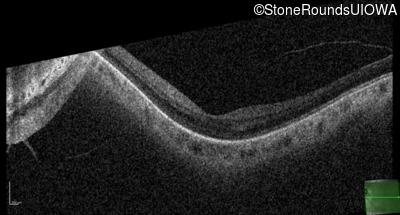

Optical Coherence Tomography - Right - 20/25 -3

Exemplar / OCT Stack